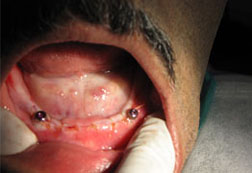

A dental implant is a titanium rod that is gently placed directly into the jawbone to act as an anchor to support one or more crowns or a denture. Each implant can usually be used to support up to two false teeth.

Implants can also be used as anchors to improve the stability and retention of loose dentures. Patients find great improvements during speech and eating, increased comfort and renewed confidence. We can often remove the tooth and fit a dental implant at the same appointment